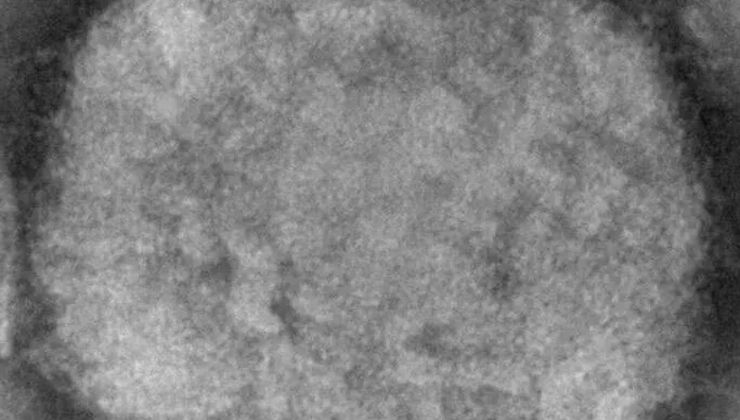

ABD’de çocuklar arasında ilk maymun çiçeği vakaları

ABD Hastalık Kontrol Merkezinden (CDC) yapılan açıklamaya göre ülkede maymun çiçeğine ilk kez çocuklar arasında rastlandı. Çocuklardan birinin California’da, diğerinin ise Washington DC’ye gelen ancak ülkede ikamet etmeyen bir bebek olduğu belirtildi. İki vakanın birbiriyle bağlantısız olduğu, çocukların muhtemelen ev içi bulaşma sonucu enfekte oldukları aktarıldı. Her ikisinin de sağlık durumunun iyi olduğu, tedavi altına alındığı vurgulandı.

8 yaşın altındaki çocukların şiddetli maymun çiçeği virüsü riski altında olduğunu ifade edilirken, şu ana kadar ülke genelinde 2 bin 500’den fazla vaka kaydedildi.